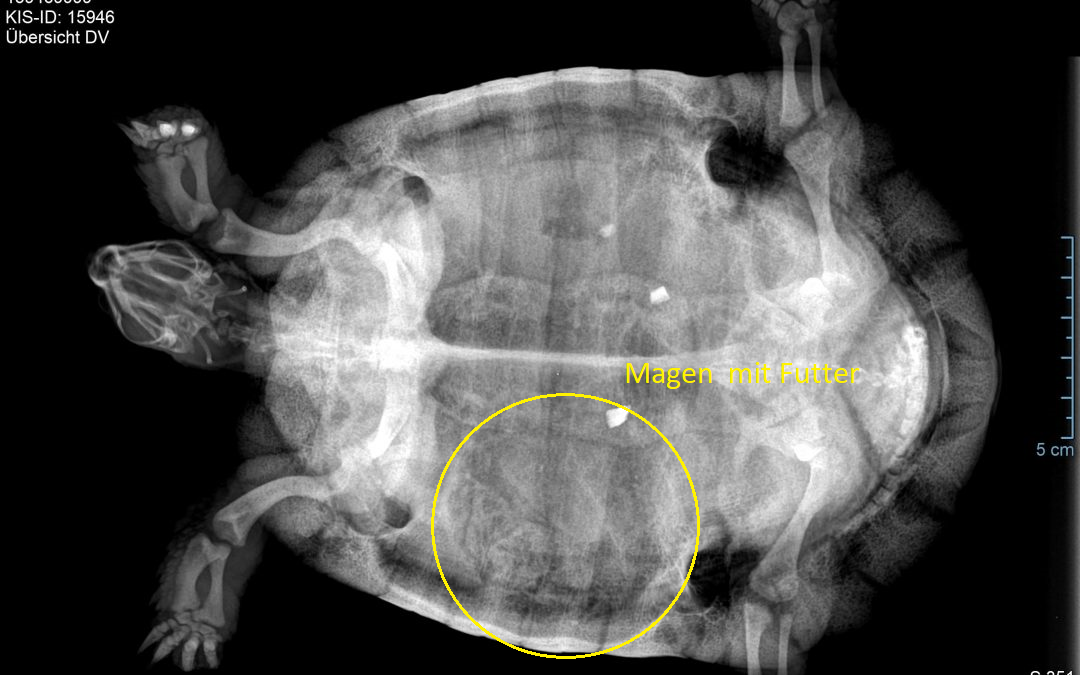

In Jedem Fall ist eine Blut­un­ter­su­chung /“Reptilienprofil” anzu­ra­ten und ein Rönt­gen. Im Rönt­gen schaut man nach über­gan­ge­nen Eiern Bla­sen­stei­nen und der Kno­chen­struk­tur. Bei weib­li­chen Krö­ten soll­te man aber immer den­noch auch an Fol­li­kel den­ken, die man im Rönt­gen nicht erken­nen kann. Da die­se Fol­li­kel immer zu einer Bauch­fell­ent­zün­dung füh­ren, müs­sen die­se raus. Meist geht das durch einen Haut­schnitt in der Knie­fal­te, den Pan­zer braucht man dazu nicht eröff­nen